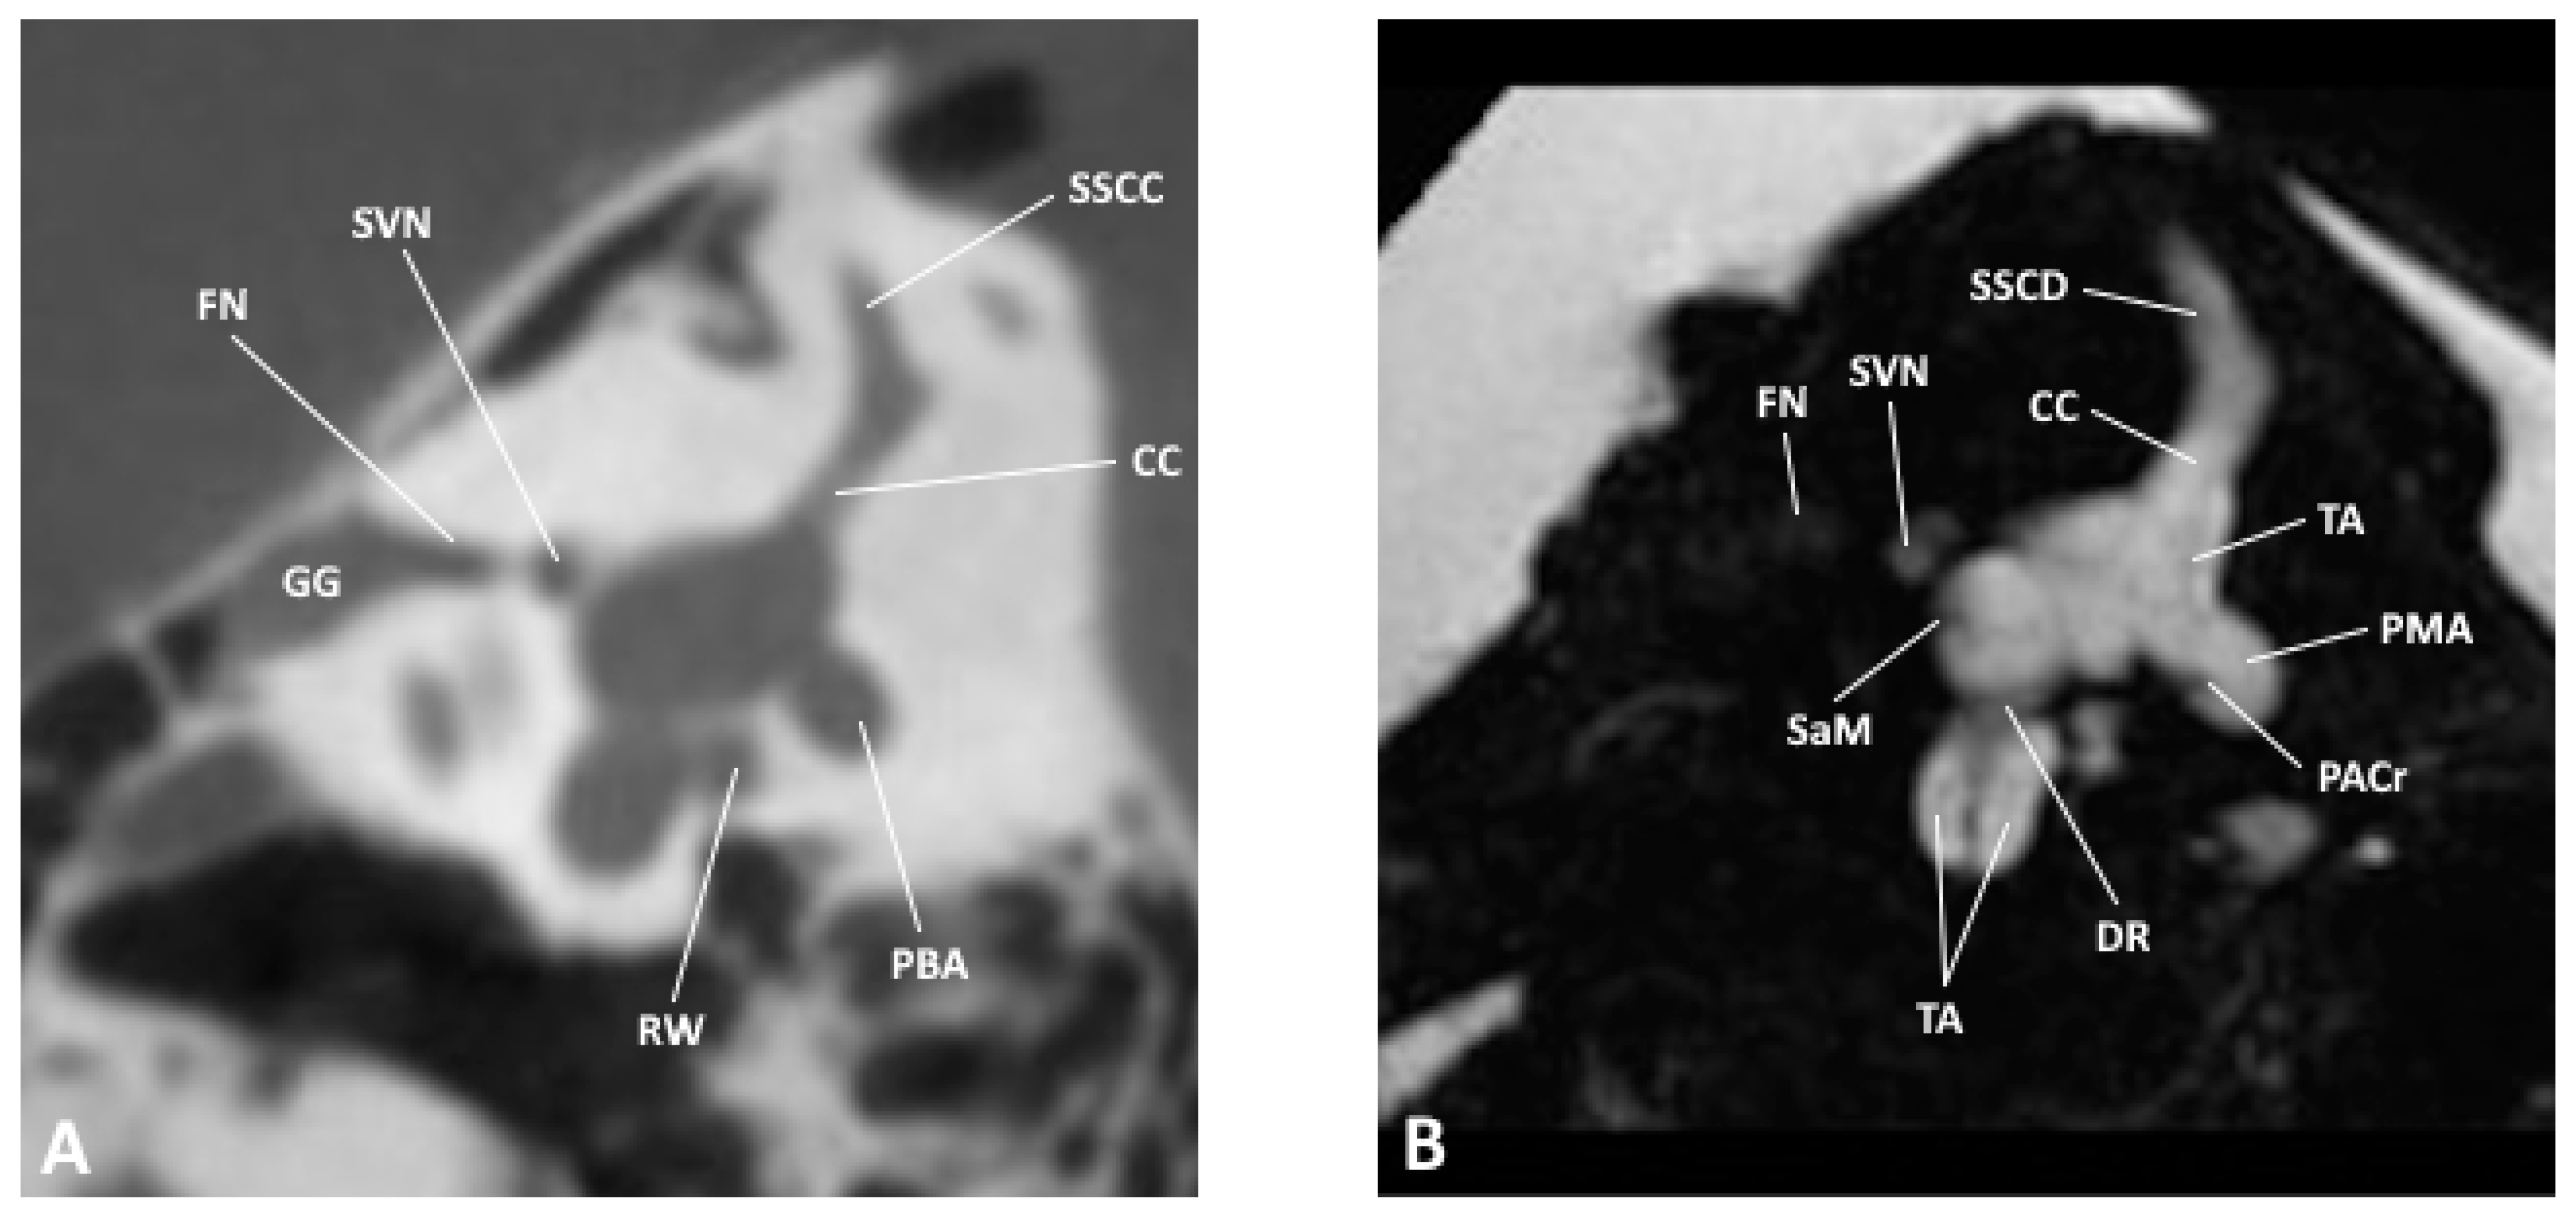

Figure 1. Axial slice through the inner and middle ear at the level of the round window as observed by (A) CBCT and (B) MRI; CoAq, cochlear aqueduct; ISJ, incudostapedial joint; M, malleus; RW, round window; SL, spiral lamina; ST, scala tympani; SV, scala vestibuli; TA, truncation artifact; TT, tensor tympani.